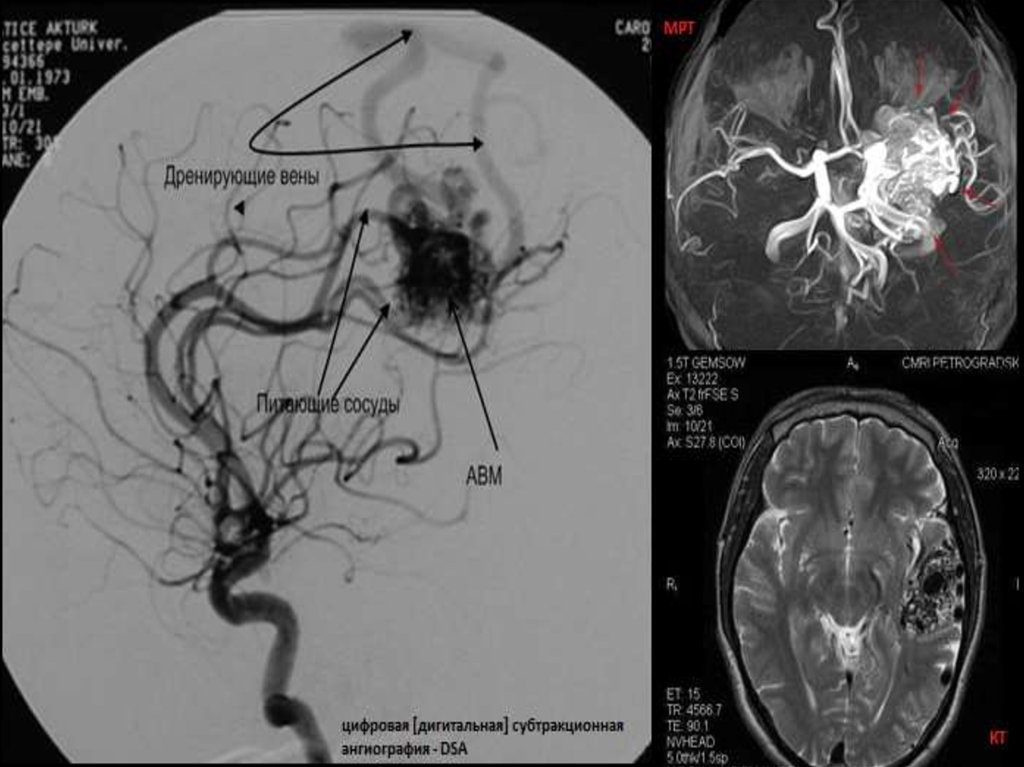

4.

Наиболее точный

метод — контрастная

ангиография.

Внутривенно вводится

контрастное

вещество, затем

делают несколько

рентгеновских снимков

черепа в разных

проекциях. Методика

связана с выраженным

риском осложнений,

поэтому применяется

только в крайних

случаях.

Селективная ангиография — через катетер контраст вводится

непосредственно к очагу мальформации.